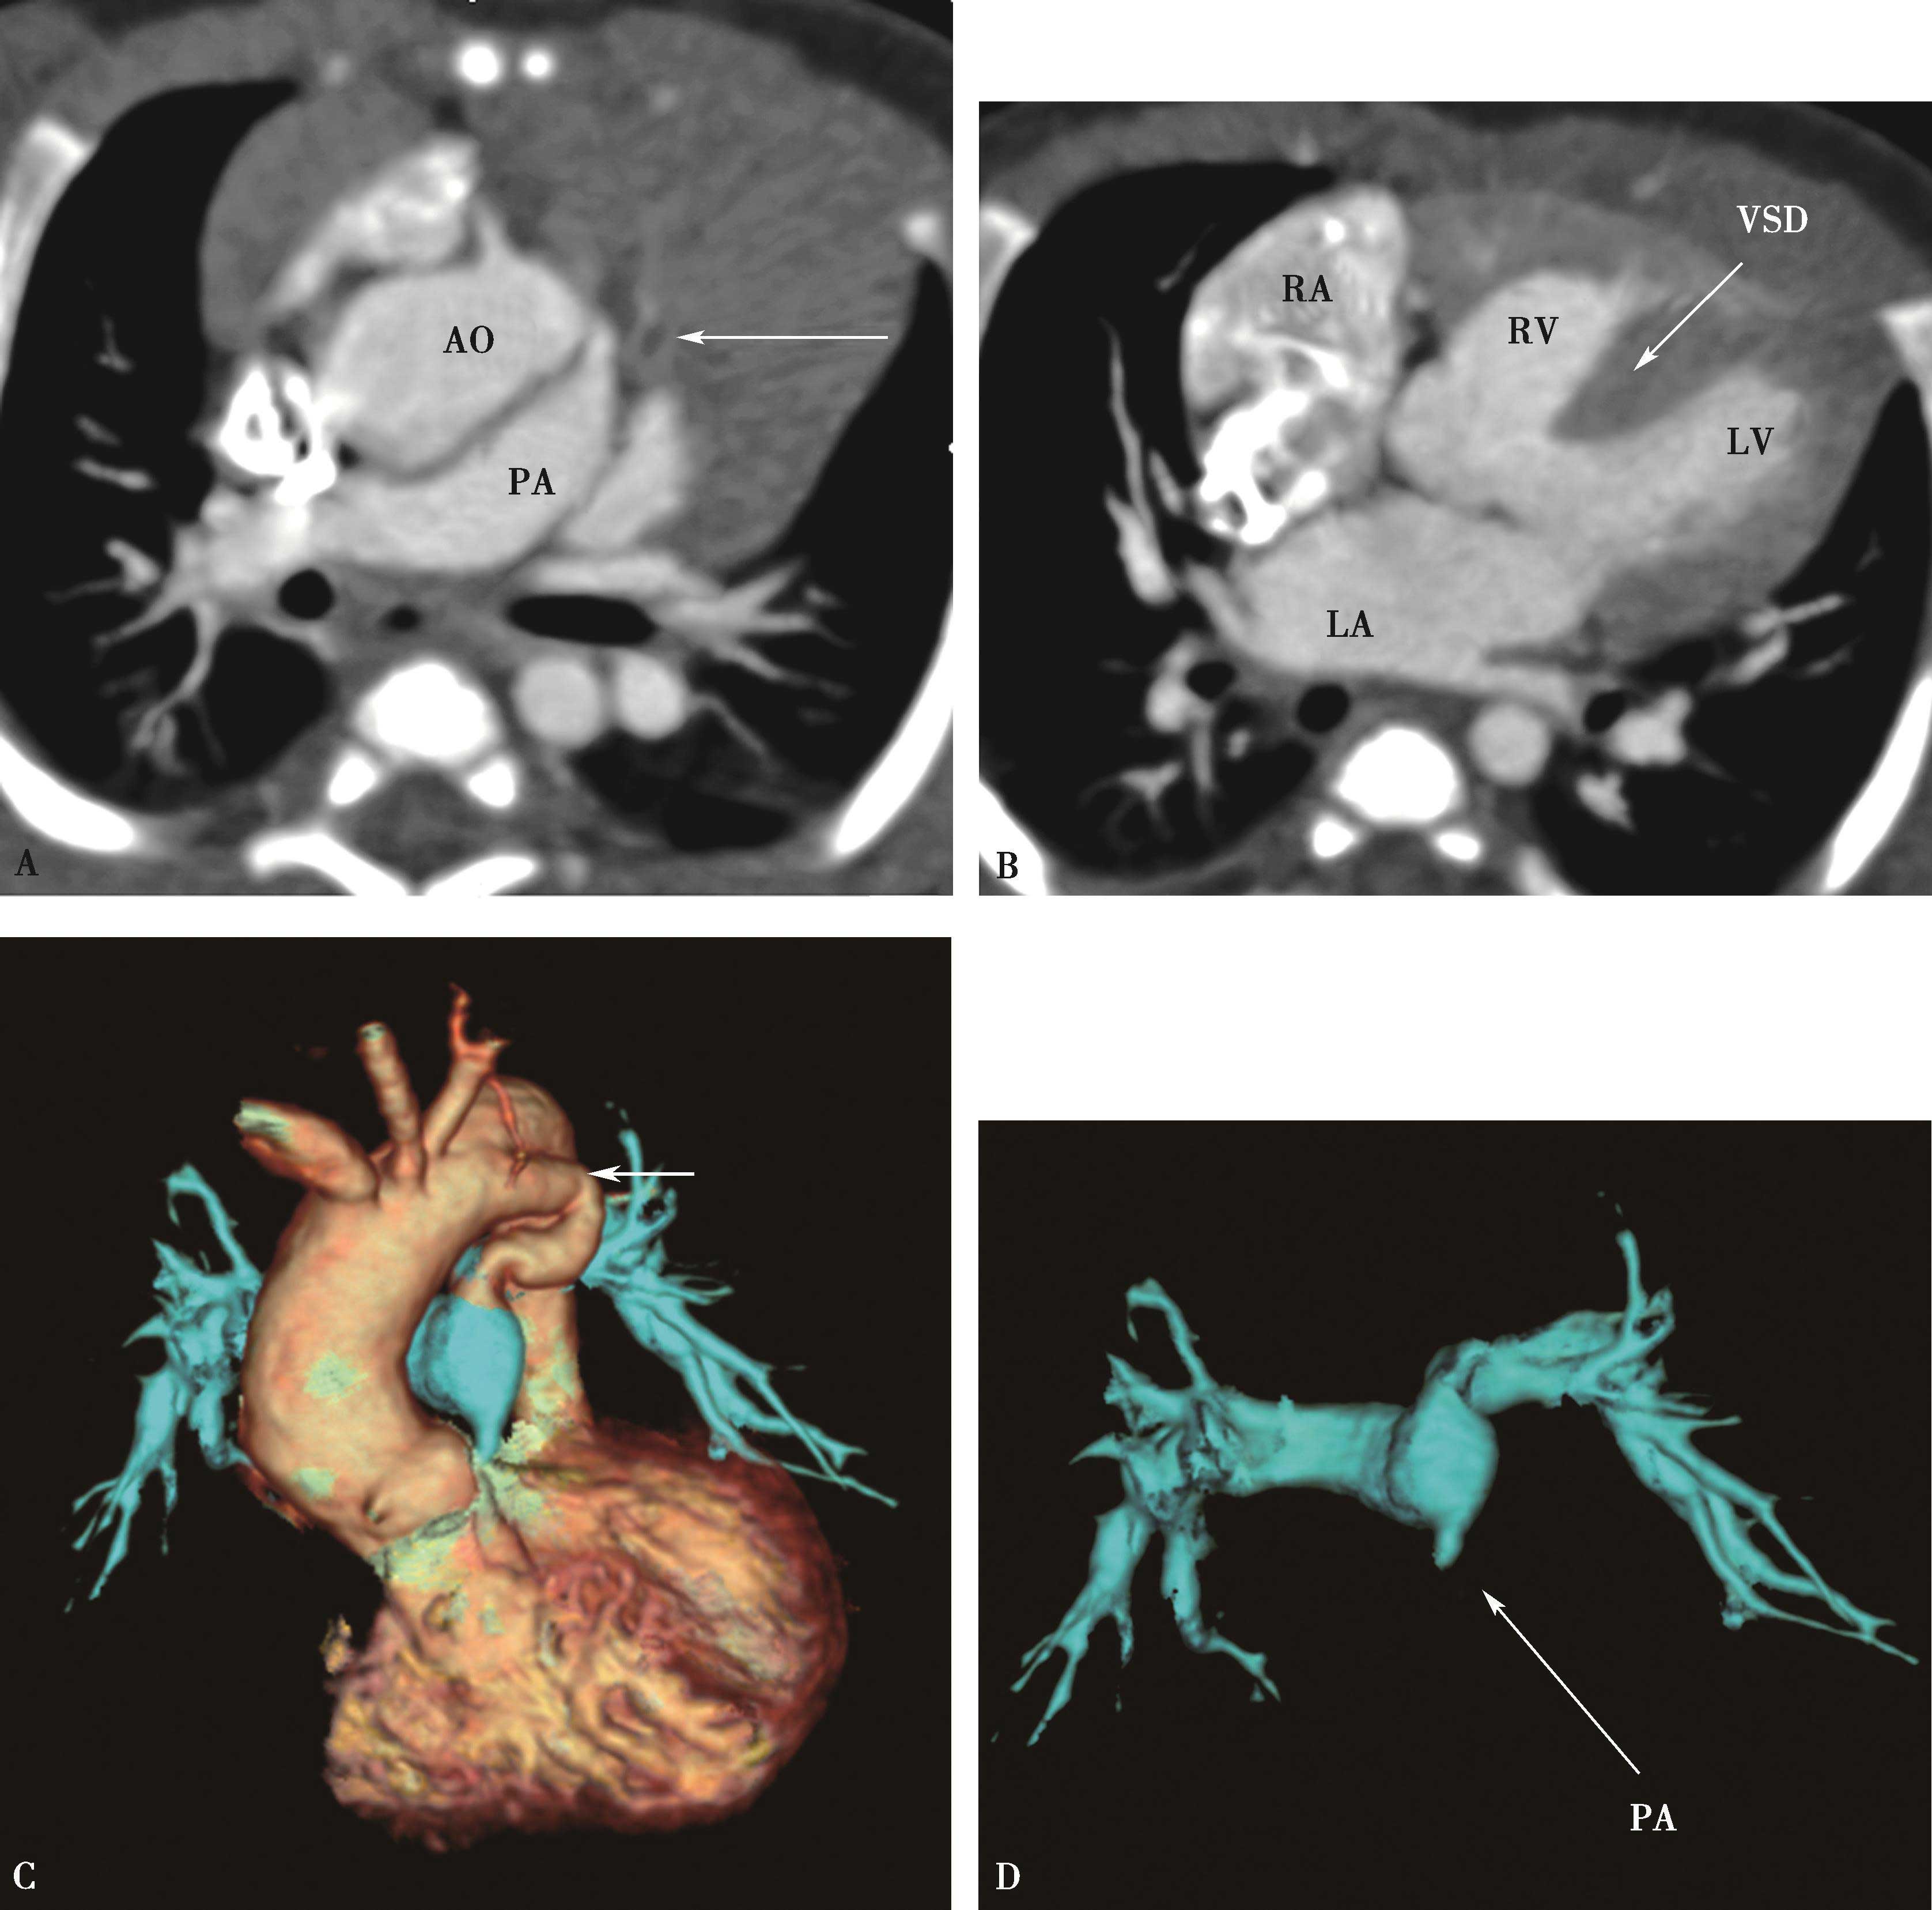

图8-8-3 女,21岁。活动后心慌气短15年,先天性心脏病,室间隔缺损(VSD),重度肺动脉高压

A、B.多层重组,示主肺动脉高度瘤样扩张,可见左侧壁线状内膜片影,为肺动脉夹层(↑);C.三维重建,容积再现示主肺动脉夹层(↑)。MPA:主肺动脉;RPA:右肺动脉;LPA:左肺动脉